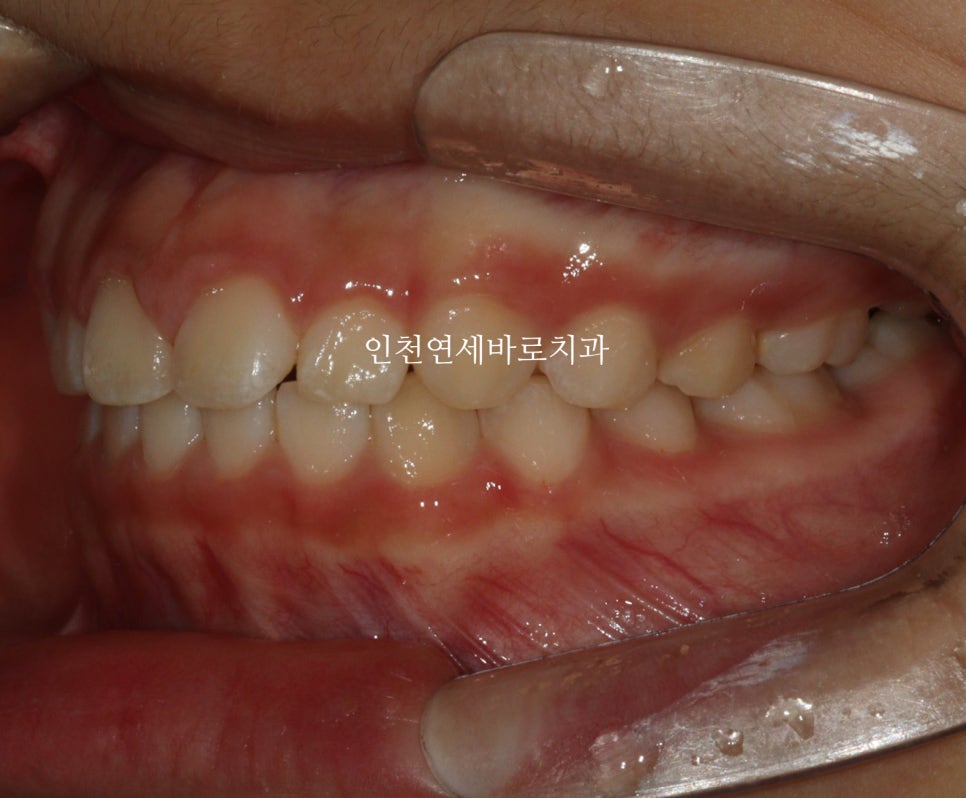

14주 후 결과

거의완성되었습니다.

거의 라고 말하는 이유는 저희 의료진 눈에는 아주아주 미세한 부분이 마음에 들진 않아서요.

인비절라인 라이트는 1년이라는 기간안에 1회 재제작이 아주 저렴한 비용으로 가능합니다.

이 친구도 정기검진을 하고 25.1.월쯤 아주미세한 부분의 수정을 위해 재제작을 하기로 했어요.

화살표 부분이 약간 아쉬웠기 때문입니다.

저런건 4주정도면 충분하죠.

조금 더 활짝 웃게 된 아이입니다.